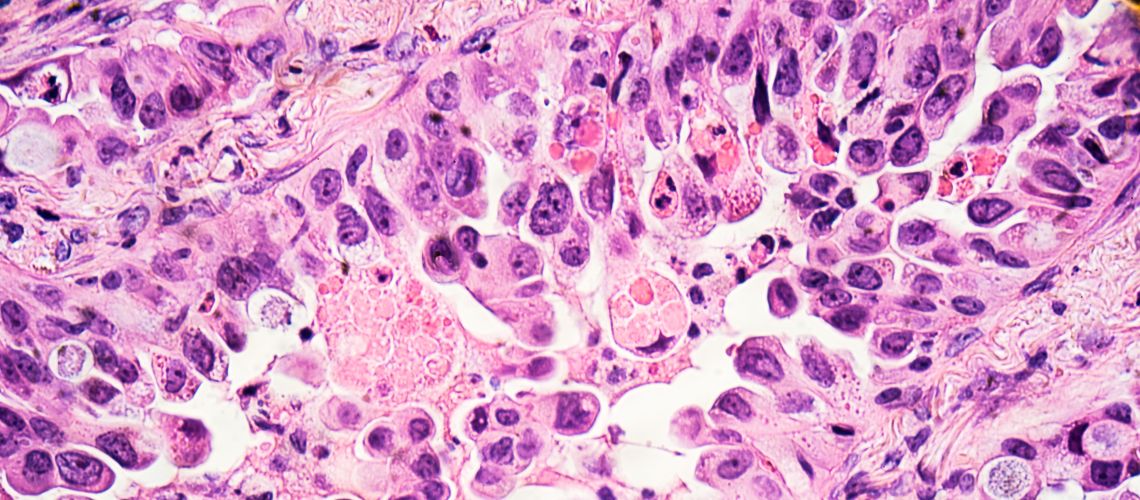

Cancer of Unknown Primary (CUP) occurs when cancer spreads from its primary source to another part of the body, but the primary source remains unknown. The difficulty surrounding determining the cancer’s origin means that patients often don’t get a definitive diagnosis.

It is the sixth highest cause of cancer death in the UK and Australia but due to the insufficient understanding of its biology, an absence of reliable biomarkers, and disagreement over its diagnosis and management, the treatment options are limited and patient prognosis is generally poor.